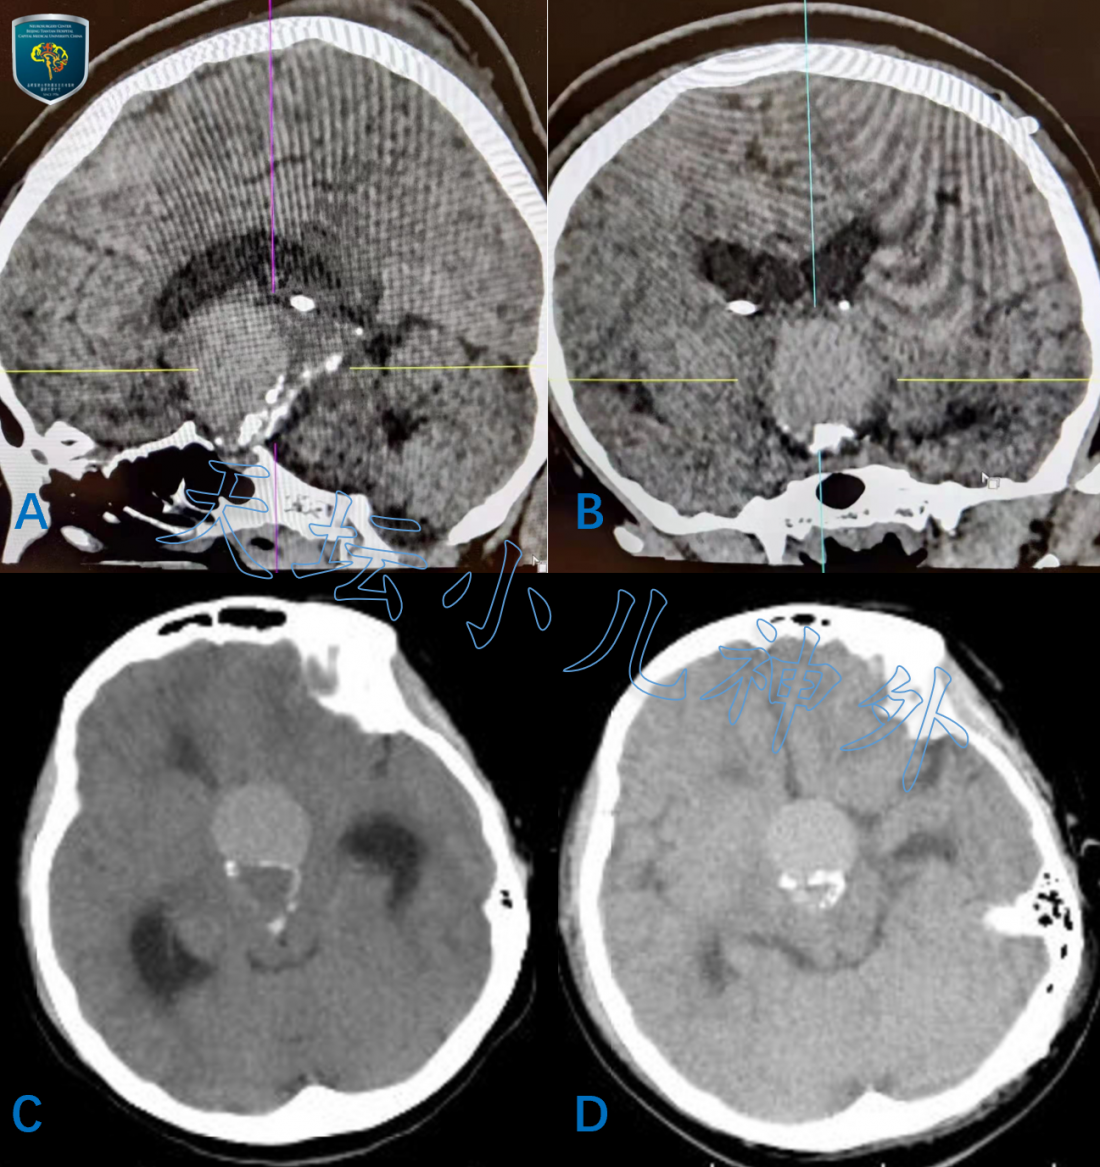

2020年11月接诊一例来自山东莒县12岁女性患儿(158cm,52.0kg),主诉:间断头痛1月,双眼视力下降5天。当地医院检查示巨大鞍区占位,遂来我院就诊。门诊查体示:神清语利,自主体位,双眼视力下降,眼前20cm数指,双瞳等大、光反应灵敏,余神经系统查体阴性。术前激素水平正常;头颅CT平扫显示:鞍区囊实性占位伴钙化,梗阻性脑积水伴室旁水肿,颅咽管瘤?(图1)。MRI显示:蝶鞍扩大,鞍上囊实性占位突入第三脑室,视交叉受压,长圆形混杂信号影,边界清晰,大小约40*25*25mm,囊壁不均匀强化,颅咽管瘤可能性大(图2)。